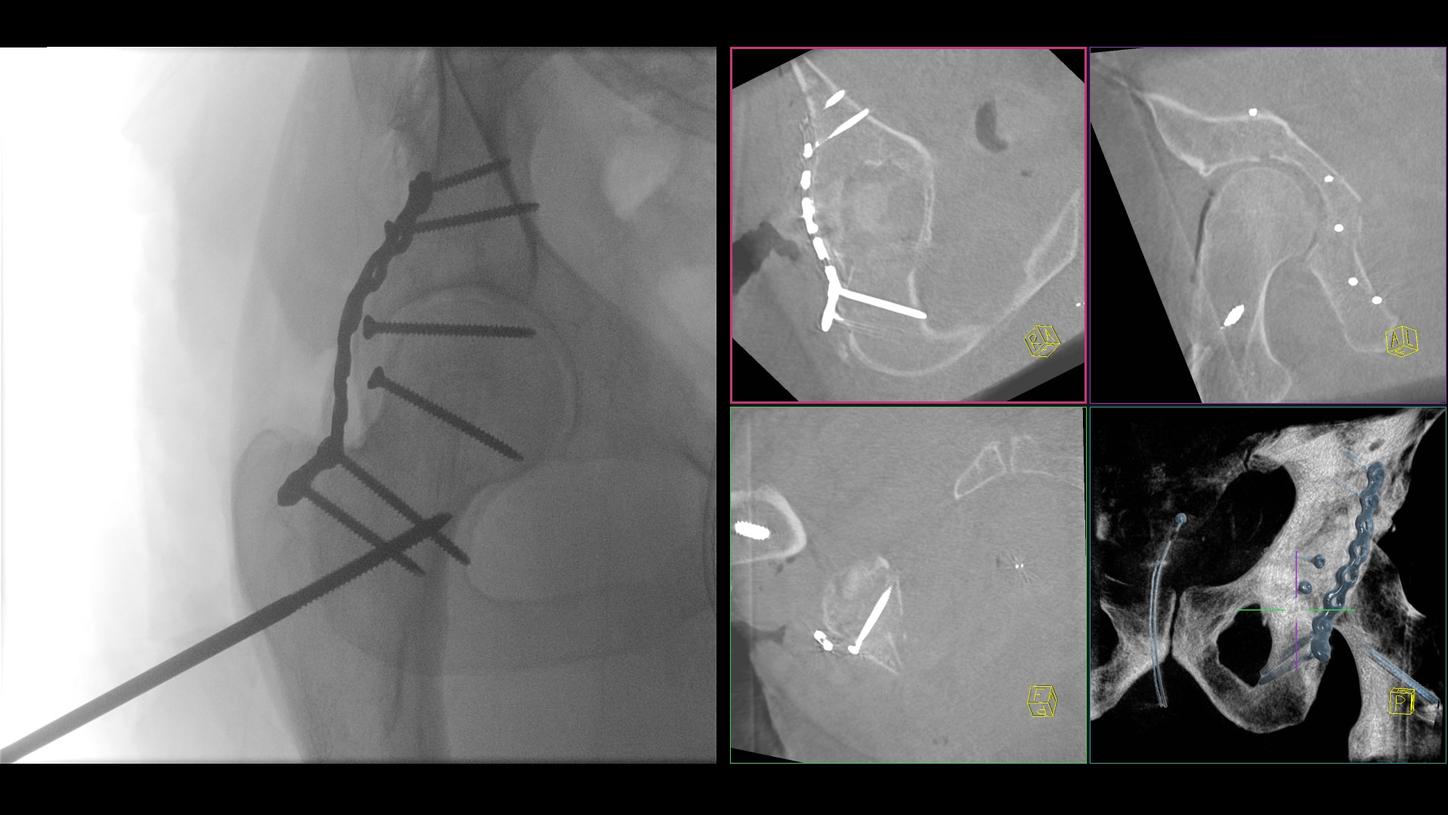

A preclinical study confirmed intraoperative-imaging time savings of up to 55% in pelvic surgery, enabled by the self-driving and automation technologies of CIARTIC Move.

CIARTIC Move already has proven its benefits in a preclinical study1: The system enabled significant time savings for all three anatomical regions included in the study (pelvis, spine, distal radius).

A preclinical study confirmed intraoperative-imaging time savings of up to 55% in pelvic surgery, and proved that a single person could operate the system independently from inside the sterile field.